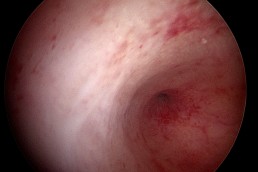

Aspectul normal al cavității uterine

În mod normal, cavitatea uterină are pereți netezi și este lipsită de fibroame, țesut cicatricial, malformații congenitale sau polipi (Fig.1). Simultan cu inspecția aspectului pereților uterini se vizualizează și originea trompelor uterine (dreaptă și stângă) – Fig. 2